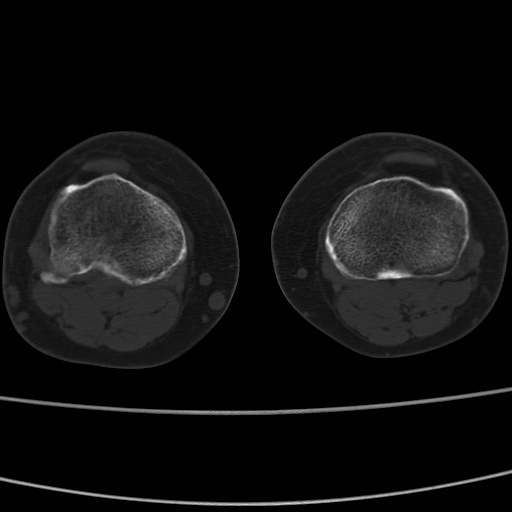

女性,50岁。【请提供患者临床症状体征】

右膝关节退行性改变,关节游离鼠。

右膝关节退行性改变,滑膜黏液囊钙/骨化并游离。